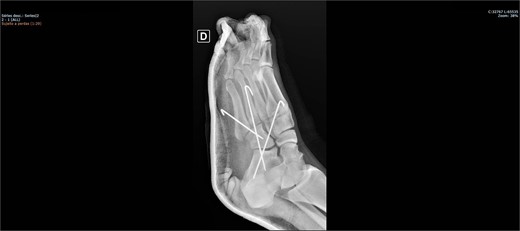

The patient was placed on the surgical table in the supine position, anesthetized with spinal anesthesia, and given prophylactic antibiotic therapy with 2 g of cefazolin. After exsanguination of the lower limb, a dorsolateral incision was made on the foot over the cuboid bone and deepened through the layers until complete visualization of the cuboid bone was achieved. There was an interposition of ligamentous structures, such as the calcaneocuboid ligament, dorsal cuneocuboid ligament, and dorsal tarsometatarsal ligaments. After removing all structures that were interposed and preventing reduction, the cuboid was reduced easily, but instability was observed. Due to the instability found, percutaneous fixation was performed with three Kirschner wires: the first extending from the fourth metatarsal to the calcaneus, traversing the cuboid; the second from the fifth metatarsal to the cuboid; and the third from the cuboid to the calcaneus, from anterior-dorsal to posterior-plantar (Figs 3 and 4). After complete fixation, the stability of the cuboid was observed, maintaining it in the correct position, confirmed with fluoroscopy during surgery.